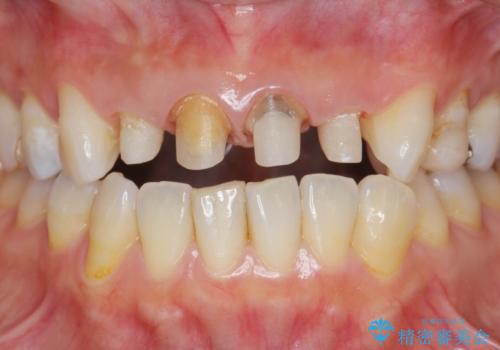

- 「黒ずんで、見栄えの悪い前歯をきれいにしたい。」と、前歯のセラミック治療を希望され来院されました。

全て根管治療のすでになされている歯の変色で、オールセラミッククラウンによる審美性の改善を計画します。

- 52.8万円(ジルコニアクラウン×4・仮歯×4)費用は治療当時の料金となります